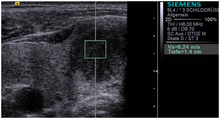

Acoustic Radiation Force Impulse (ARFI) Imaging is a type of ultrasound elastography used in medicine, particularly for the diagnosis and monitoring of cancers. ARFI imaging uses acoustic radiation force to generate images of the mechanical properties of soft tissue.

Yoneda et al. also recently compared ARFI shear wave imaging as implemented on the Siemens Acuson S2000 with transient elastography using the FibroScan system (EchoSens, Paris, France) in the context of evaluating patients with Non-alcoholic Fatty Liver Disease (NAFLD).[2]